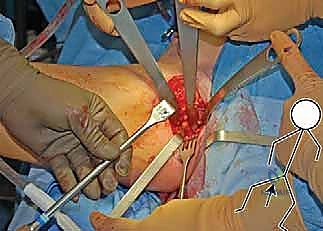

4. إعادة التوجيه والتدوير (Rotation & Redirection)

باستخدام أدوات خاصة، يقوم الدكتور هطيف بتدوير التجويف الحقي الحر في ثلاثة أبعاد (للأمام، وللخارج، وللأسفل) حتى يغطي رأس عظم الفخذ بشكل مثالي وميكانيكي سليم. يتم التحقق من الزاوية الجديدة فوراً داخل غرفة العمليات باستخدام جهاز الأشعة السينية المتحرك (C-arm).

5. التثبيت القوي (Fixation)

بمجرد الوصول إلى الوضع المثالي، يتم تثبيت العظام في مكانها الجديد باستخدام براغي معدنية قوية من التيتانيوم أو دبابيس (K-wires). هذا التثبيت يضمن التحام العظام بشكل صحيح خلال فترة التعافي.